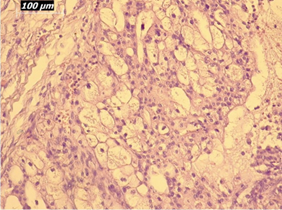

Renal artery embolization was performed under local anesthesia using the Seldinger technique, with complete occlusion confirmed angiographically (Figures 3-4). Six days later, a transabdominal left radical nephrectomy was performed. Intraoperatively, the kidney appeared markedly enlarged and deformed, containing cystic and soft-tissue components but without invasion of adjacent structures (Figures 5-6). The operation was uneventful, with minimal blood loss (approximately 300 mL) and no transfusion requirement. The postoperative course was smooth, and the patient was discharged on postoperative day five in good condition. Histopathological examination revealed that the upper pole lesion corresponded to a low-grade clear cell RCC with focal necrosis (Figures 7-8). The larger lesion was identified as a well-differentiated liposarcoma (Figures 9-10), correcting the initial radiologic misdiagnosis of angiomyolipoma. At the three-month follow-up, the patient remained asymptomatic. Laboratory results indicated mild renal impairment (creatinine 169 µmol/L, urea 9.2 mmol/L) but normal inflammatory markers. Ultrasonography revealed no recurrence or lymphadenopathy. Nephrology follow-up was continued due to reduced renal function. Six months postoperatively, CT imaging of the thorax, abdomen, and pelvis demonstrated no evidence of local recurrence or distant metastasis. Given the absence of standardized surveillance protocols for synchronous RCC and WDLPS, followup was conducted in accordance with conventional RCC and retroperitoneal sarcoma guidelines.

Figure 10: Higher-magnification view (20×) of liposarcoma showing mature adipocytes and minimal atypia.